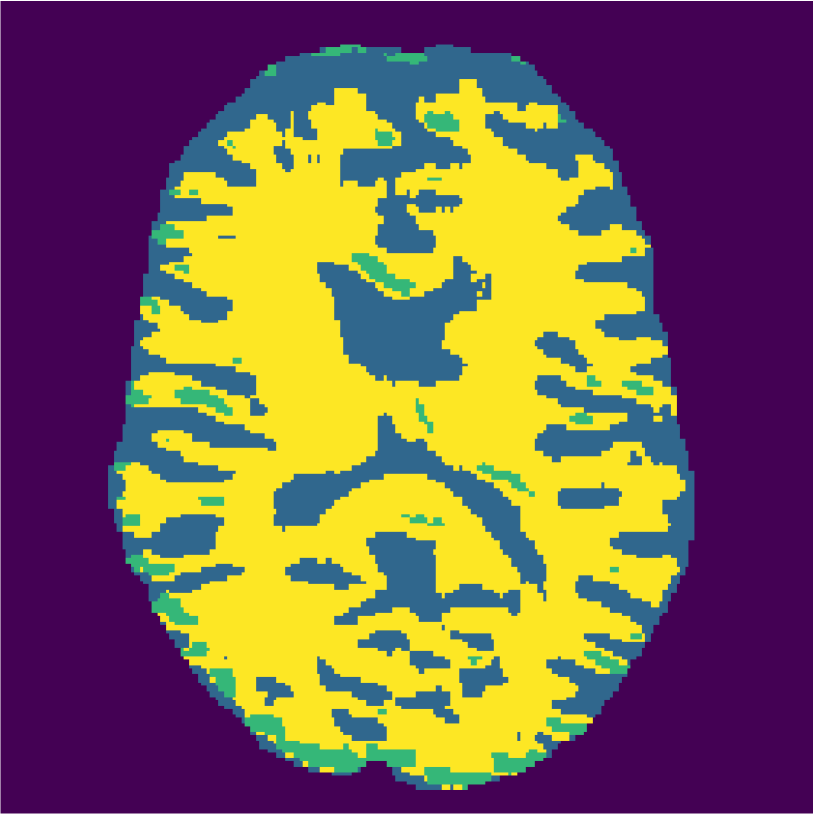

Examples of the segmentation results on one of the target test images are shown in Figure 8 for experiment 2.1, Figure 9 for experiment 2.2, and Figure 10 for experiment 2.3. Examples are shown after using 1 target patch per tissue for training, and after using 100 target patches per tissue for training. The results show that only the mrai-net classifier is able to predict a segmentation that approaches the ground truth with only 1 target patch per tissue for training (error for experiment 2.1 = 0.269, experiment 2.2 = 0.403, experiment 2.3 = 0.320), while the source and target classifiers cannot (source error for experiment 2.1 = 0.667, experiment 2.2 = 0.653, experiment 2.3 = 0.435; target error for experiment 2.1: 0.591, experiment 2.2: 0.614, experiment 2.3 = 0.596). After using 100 patches the source and target classifiers can predict a gross segmentation of WM, GM and CSF (source error for experiment 2.1 = 0.213, experiment 2.2 = 0.384, experiment 2.3 = 0.363; target error for experiment 2.1: 0.205, experiment 2.2: 0.368, experiment 2.3 = 0.368), but the mrai-net classifier prediction shows more details and a lower tissue classification error (error for experiment 2.1 = 0.111, experiment 2.2 = 0.276, experiment 2.3 = 0.284).